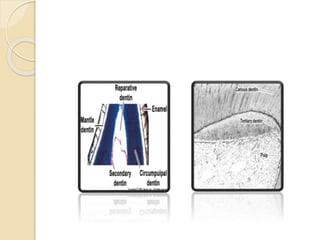

III. Tertiary dentin:

 Other names are reparative , reactive or irregular secondary

dentin

 Localized area of dentin formed opposite to reaction to

stimulus as, trauma, caries, attrition, abrasion and restorative

procedures.

 Formed by odontoblast cell directly affected by stimulus but

if the odontoblast are severed or dead it will replaced by

underlying U.M.C

 Histologically, D.T are few in number, irregular arrangement

(twisted)

 Dentin formation can be rapid as odontoblast are included in

reparative dentin (osteodentin) or not contain D.T. as in

atrubular Dentin.

 It separated from other dentin types by deeply stain line.